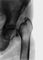

Диагноз. Важнейшую роль в диагностике О. с. отводят рентгенологическому исследованию, при котором отмечают снижение плотности тени костей (остеопения), усиление вертикальной исчерченности тел позвонков, склероз субхондральных пластинок, многочисленные вдавленные переломы в центральных отделах субхондральных пластинок, переломы тел позвонков (рис. 1), костей таза, шеек бедренных костей, других костей скелета. Характерны также истончение кортикального слоя длинных трубчатых костей, перестроечные процессы по типу зон Лоозера в шейках бедренных костей (рис. 2) и костях таза. В некоторых случаях наблюдаются зернистые очаги просветления в длинных трубчатых костях, а также в костях черепа и кистей.

При некоторых формах О. с. возможны особенности рентгенологические картины. Так, при стероидной форме болезни в отличие от постменопаузальной чаще встречается деформация тел позвонков по типу рыбьих (рис. 3). Клиновидная деформация тел позвонков у больных с постменопаузальной формой возникает без видимой травмы, а при О. с. у лиц молодого и среднего возраста подобная деформация тел позвонков может выявляться после подъема тяжести или падения с высоты своего роста. Многочисленные компрессионные переломы тел позвонков, которые ранее описывали как гормональную спондилопатию или остеопоротическую спондилопатию, целесообразнее обозначать как платиспондилию с учетом того, что подобная рентгенологическая картина может наблюдаться не только при различных формах О. с., но и при других заболеваниях и метаболических остеопатиях. Как правило, связи подобной деформации тел позвонков с эндокринными нарушениями не отмечается. Переломы шеек бедренных костей чаще встречаются у больных с сенильной формой О. с., а костей таза — у лиц молодого и среднего возраста. Ни один из рентгенологических симптомов не является патогномоничным, т.к. подобные изменения могут отмечаться при остеомаляции, остеопоротической форме миеломной болезни и др. В связи с этим рентгенологические изменения, как и клинические, должны рассматриваться только в совокупности с другими данными.